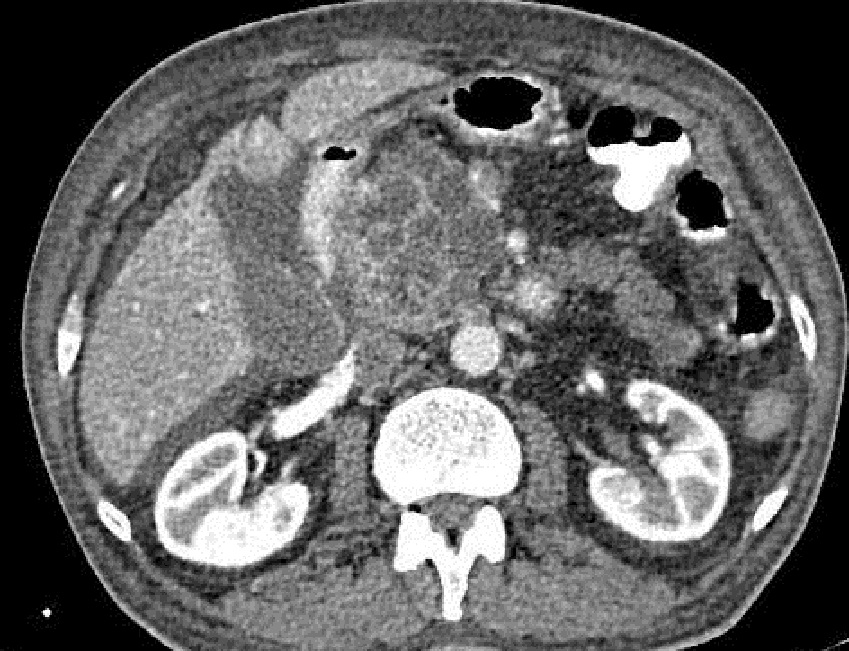

Aspect radiologique de

malignite metastatique loco- regionale d'une

tumeur intracanalaire

papillaire et mucineuse du pancréas ( TIPMP ) .

La tumeur de la tete du pancreas est volumineuse a

bord irregulie comporte de plusieure des kystes

hypointense . Signe de rehaussement de la tumeur et

structure interseptal kystique apres injection de

contrast peut en voyant . Image radiologique

TDM plus C+ en coupe axiale |